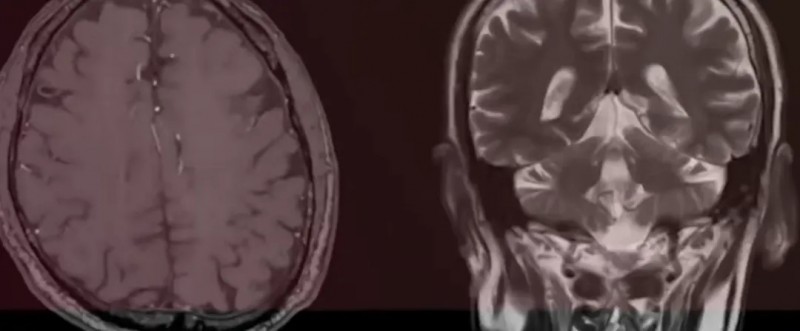

影像结果如晴天霹雳:莱昂的额叶过度发育,颅内肿瘤疯狂生长,头部肿胀得像“一头白鲸”,必须立刻手术!周二做检查,周三紧急动身术前准备,夫妻俩被卷入医疗决策的旋风,连悲伤的时间都没有。“我们根本来不及思考,只能跟着医生的脚步跑,心里只有一个念头:救救我的孩子。”

紧急开颅手术过后,莱昂的情况雪上加霜:输血、静脉破裂、颅内严重肿胀,生命体征长时间不稳定,还接连做了两次分流手术,在重症监护室整整挣扎了两周。“护士告诉我们,莱昂的病例是她们见过最令人震惊的病例之一。”那段日子,医院的仪器滴答声是夫妻俩最恐惧的声音,孩子插满管子的小小身躯,成了他们心中永远的痛。更糟的是,术后的病理结果显示,莱昂的肿瘤竟是高级别星形细胞瘤——一种侵袭性极强的恶性脑癌,预后极差,莱昂的生命进入了倒计时。